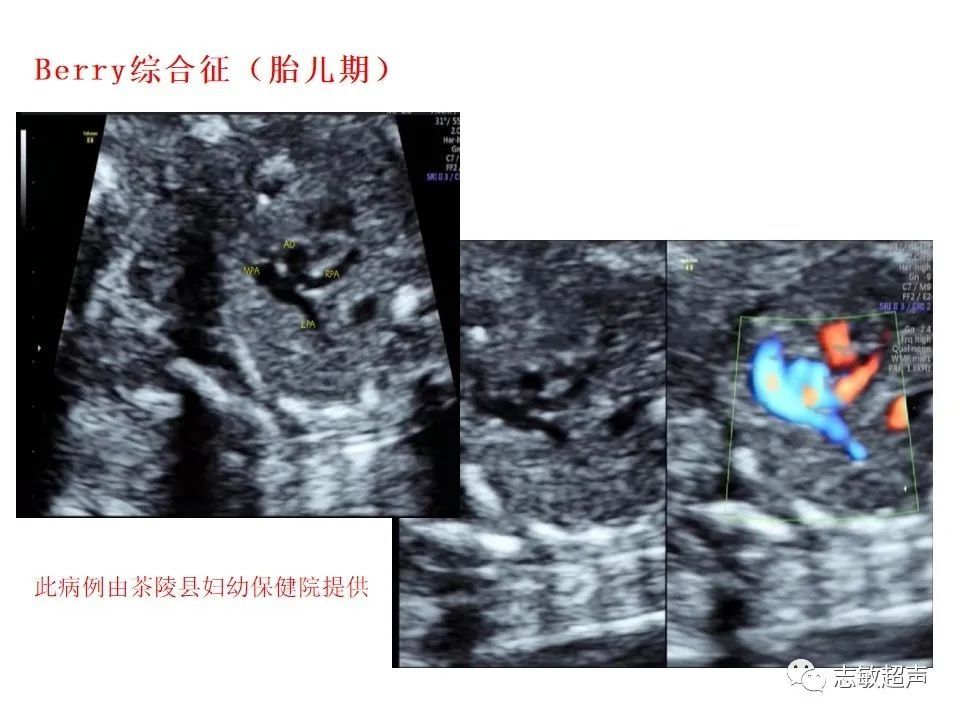

超声|肺动脉瓣周边异常血流的超声鉴别

肺动脉瓣周边的异常血流常见有: